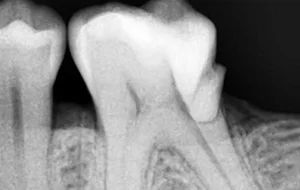

• The very first step involves an X-ray which is taken to determine the extent and approach to infection. If required local anesthesia is administered before starting the treatment.

• The next step is Cavity Preparation. A cavity is prepared, making sure all the infected tooth material or previous filling material is removed and a proper approach to inner-part of the tooth (pulp) is established.

• This is followed by disinfection and shaping of pulp canals. The infected pulp is cleared out completely, canals are shaped and cleaned. Thorough disinfection is achieved.